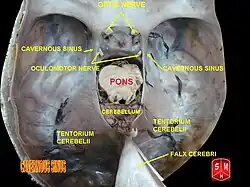

The cause of Tolosa–Hunt syndrome is not known. The disorder is thought to be, and often assumed to be, associated with inflammation of the areas behind the eyes (cavernous sinus and superior orbital fissure).[8] These granulomatous inflammations involve lymphocytes, plasma cells, and multinucleate giant cells. Clinical cases have shown that the disorder consists of the inflammation of multiple cranial nerves, with the highest prevalence of ocular motor nerves. In some cases, it also involves the inflammation of sensory nerves, specifically the trigeminal nerves.

- Inflammation around the cavernous sinus - deep in the skull behind the eyes.

MRI scans of the brain and orbit with and without contrast, magnetic resonance angiography or digital subtraction angiography and a CT scan of the brain and orbit with and without contrast may all be useful in detecting inflammatory changes in the cavernous sinus, superior orbital fissure and/or orbital apex.[3] Inflammatory change of the orbit on cross-sectional imaging in the absence of cranial nerve palsy is described by the more benign and general nomenclature of orbital pseudotumor. Sometimes a biopsy may need to be obtained to confirm the diagnosis, as it is useful in ruling out a neoplasm.[3] Other diagnoses to consider include craniopharyngioma, migraine and meningioma.[3]

Tolosa-Hunt Syndrome is highly impacted by the inflammation of the cranial nerves, especially those that are located around the cavernous sinus. These include:

Ocular Motor Nerves[8]

- Oculomotor Nerve (Cranial Nerve III) is important for eye coordination and movement. These include saccades, eye tracking, and eye fixations. This impacts 80% of patients.

- Abducens Nerve (Cranial Nerve VI) helps with moving eye muscles. Individuals can move their eyes left and right. Patients have been reported to have an impact on this nerve at least 70% of the time.

- Trochlear Nerve (Cranial Nerve IV) helps move the eye muscles downward and upward and is impacted in patients 29% of the time.

In some cases, inflammation can also impact other cranial nerves. These include:

Sensory Nerves (trigeminal nerves)[8]

- Ophthalmic branch of the trigeminal nerve (V1). This nerve is important for the forehead, eye, and upper nose. Seems to be impacted 30% of the time.

- Maxillary branch of the trigeminal nerve (V2), which is important for sensing cheeks, upper lip, and upper teeth, is occasionally impacted.

- Mandibular branch of the trigeminal nerve (V2), which impacts sensation to the lower part of the face, such as the jaw, part of the teeth, and the ability to chew, is also occasionally affected.

Tolosa-Hunt Syndrome was first recognized in 1954, when Dr. Eduardo Tolosa wrote a case study that involved inflammation of the tissues surrounding the arteries. The diagnostic tools were based on observations, as imaging and other forms of diagnosis were unavailable at the time. The patient he worked with had pain in their eyes and eye muscles. These symptoms were very similar to those of an aneurysm, with additional neurological symptoms. He found that this patient had inflammation on their carotid siphon, which can be found in the cavernous sinus.[13]